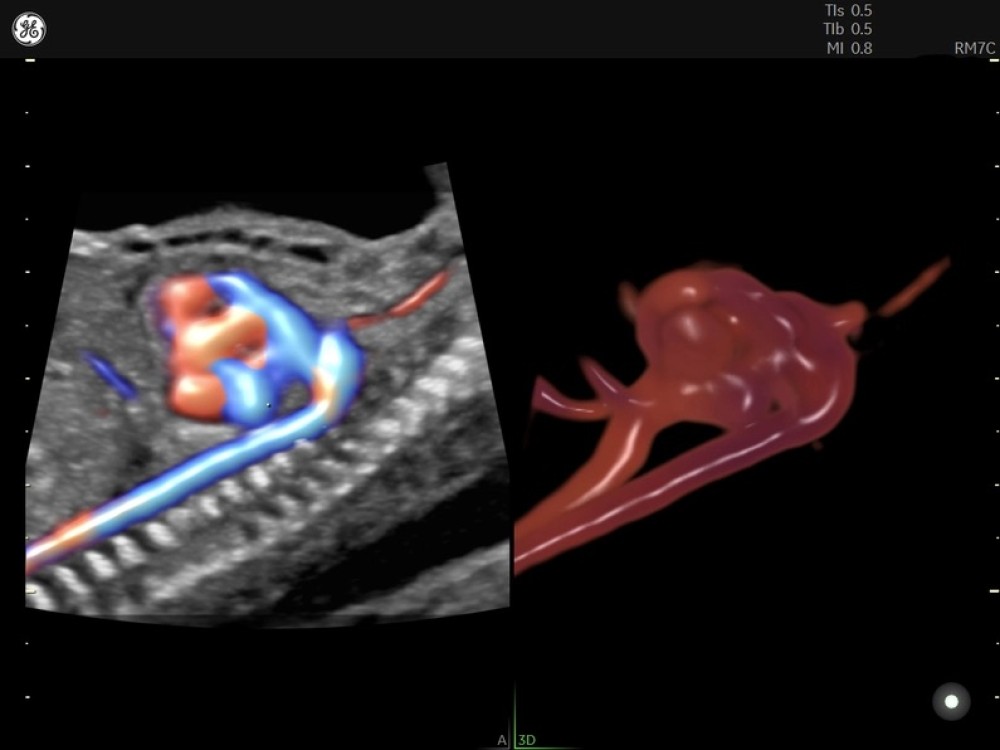

• Voluson Expert 22 real vaxtda yüksək məkan həssaslığına malik görüntülərin əldə olunmasını təmin edən avansert 4D volumetrik görüntüləmə texnologiyasından istifadə edir və bu, klinik diaqnostikanın dəqiqliyini əhəmiyyətli dərəcədə artırır.

• 3D/4D volumetrik görüntüləmə

• HDlive Studio+ (avansert render texnologiyası)

• Konveks Volumetrik Prob RAB7-D

• Konveks Matrix Volumetrik Prob RM7C

• Elektron Matrix Konveks Volumetrik Prob eM6C_Gen3